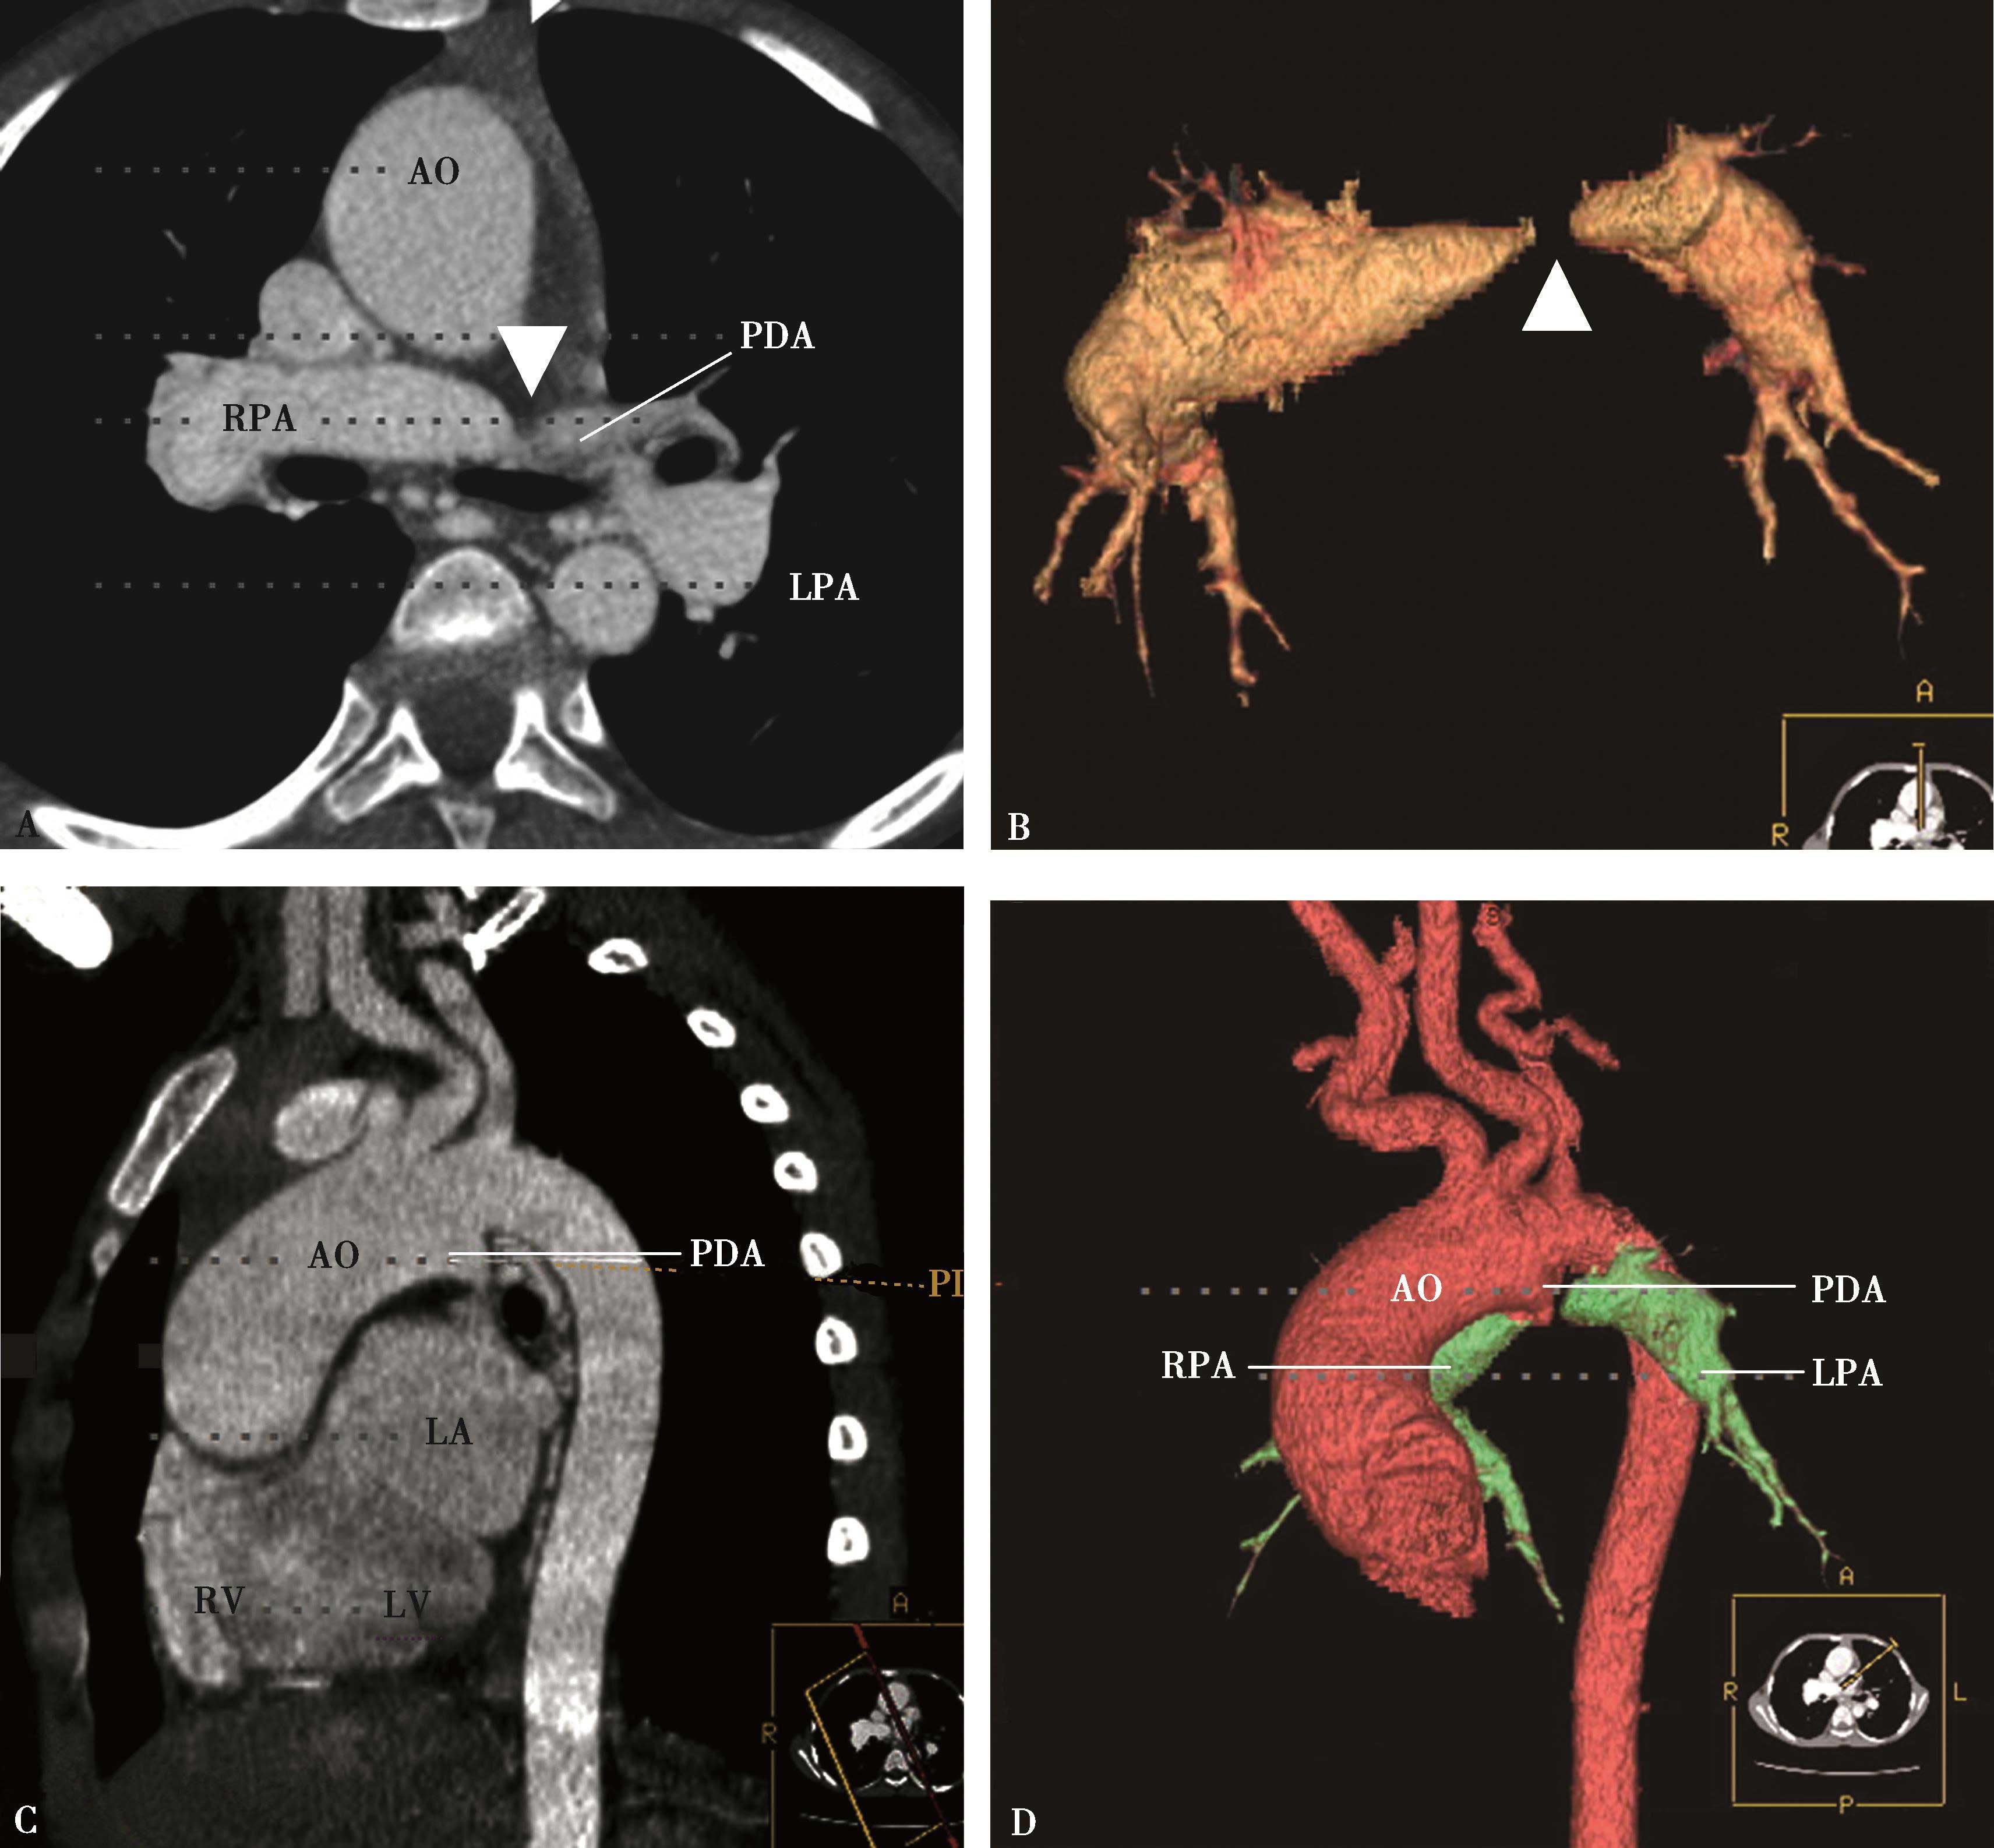

先天性心脏病:右肺动脉缺如、动脉导管未闭、肺动脉高压、肺动脉夹层(B,C,D↑)。AO:升主动脉;PA:主肺动脉;PDA:动脉导管未闭;DA:降主动脉

图8-8-2 男,33岁,肺动脉夹层(横断图像)

A、B.术前示升主动脉夹层,肺动脉夹层,可见内膜片,累及主肺动脉及右肺动脉,假腔显影较淡,管腔膨大(↑);C.升主动脉及主肺动脉血管置换术后,管腔正常(↑)。AO:升主动脉;PA:主肺动脉

图8-8-1 马方综合征,主动脉夹层,肺动脉夹层(横断图像)

图8-8-3 女,21岁。活动后心慌气短15年,先天性心脏病,室间隔缺损(VSD),重度肺动脉高压

A、B.多层重组,示主肺动脉高度瘤样扩张,可见左侧壁线状内膜片影,为肺动脉夹层(↑);C.三维重建,容积再现示主肺动脉夹层(↑)。MPA:主肺动脉;RPA:右肺动脉;LPA:左肺动脉

二、肺动脉夹层CT诊断

(一)横断图像

横断扫描是诊断的基础。肺动脉层面可见内膜片构成的线状充盈缺损,形成双腔肺动脉,亦可分辨出真腔与假腔;假腔显影较淡,管腔膨大。心包积液或胸腔积液,常预示有破裂的可能。

(二)多层重组(MPR)或曲面重组(CPR)

以不同层厚、不同角度重建肺动脉,可以清楚显示肺动脉内腔、内膜片,累及的范围及程度,有否血栓形成等,对指导治疗有重要价值。

(三)三维重建

容积再现(VR)或表面阴影显示(SSD),有助于直观肺动脉外形,对观察内腔不如多层重组能提供更多信息(图8-8-1~图8-8-3)。